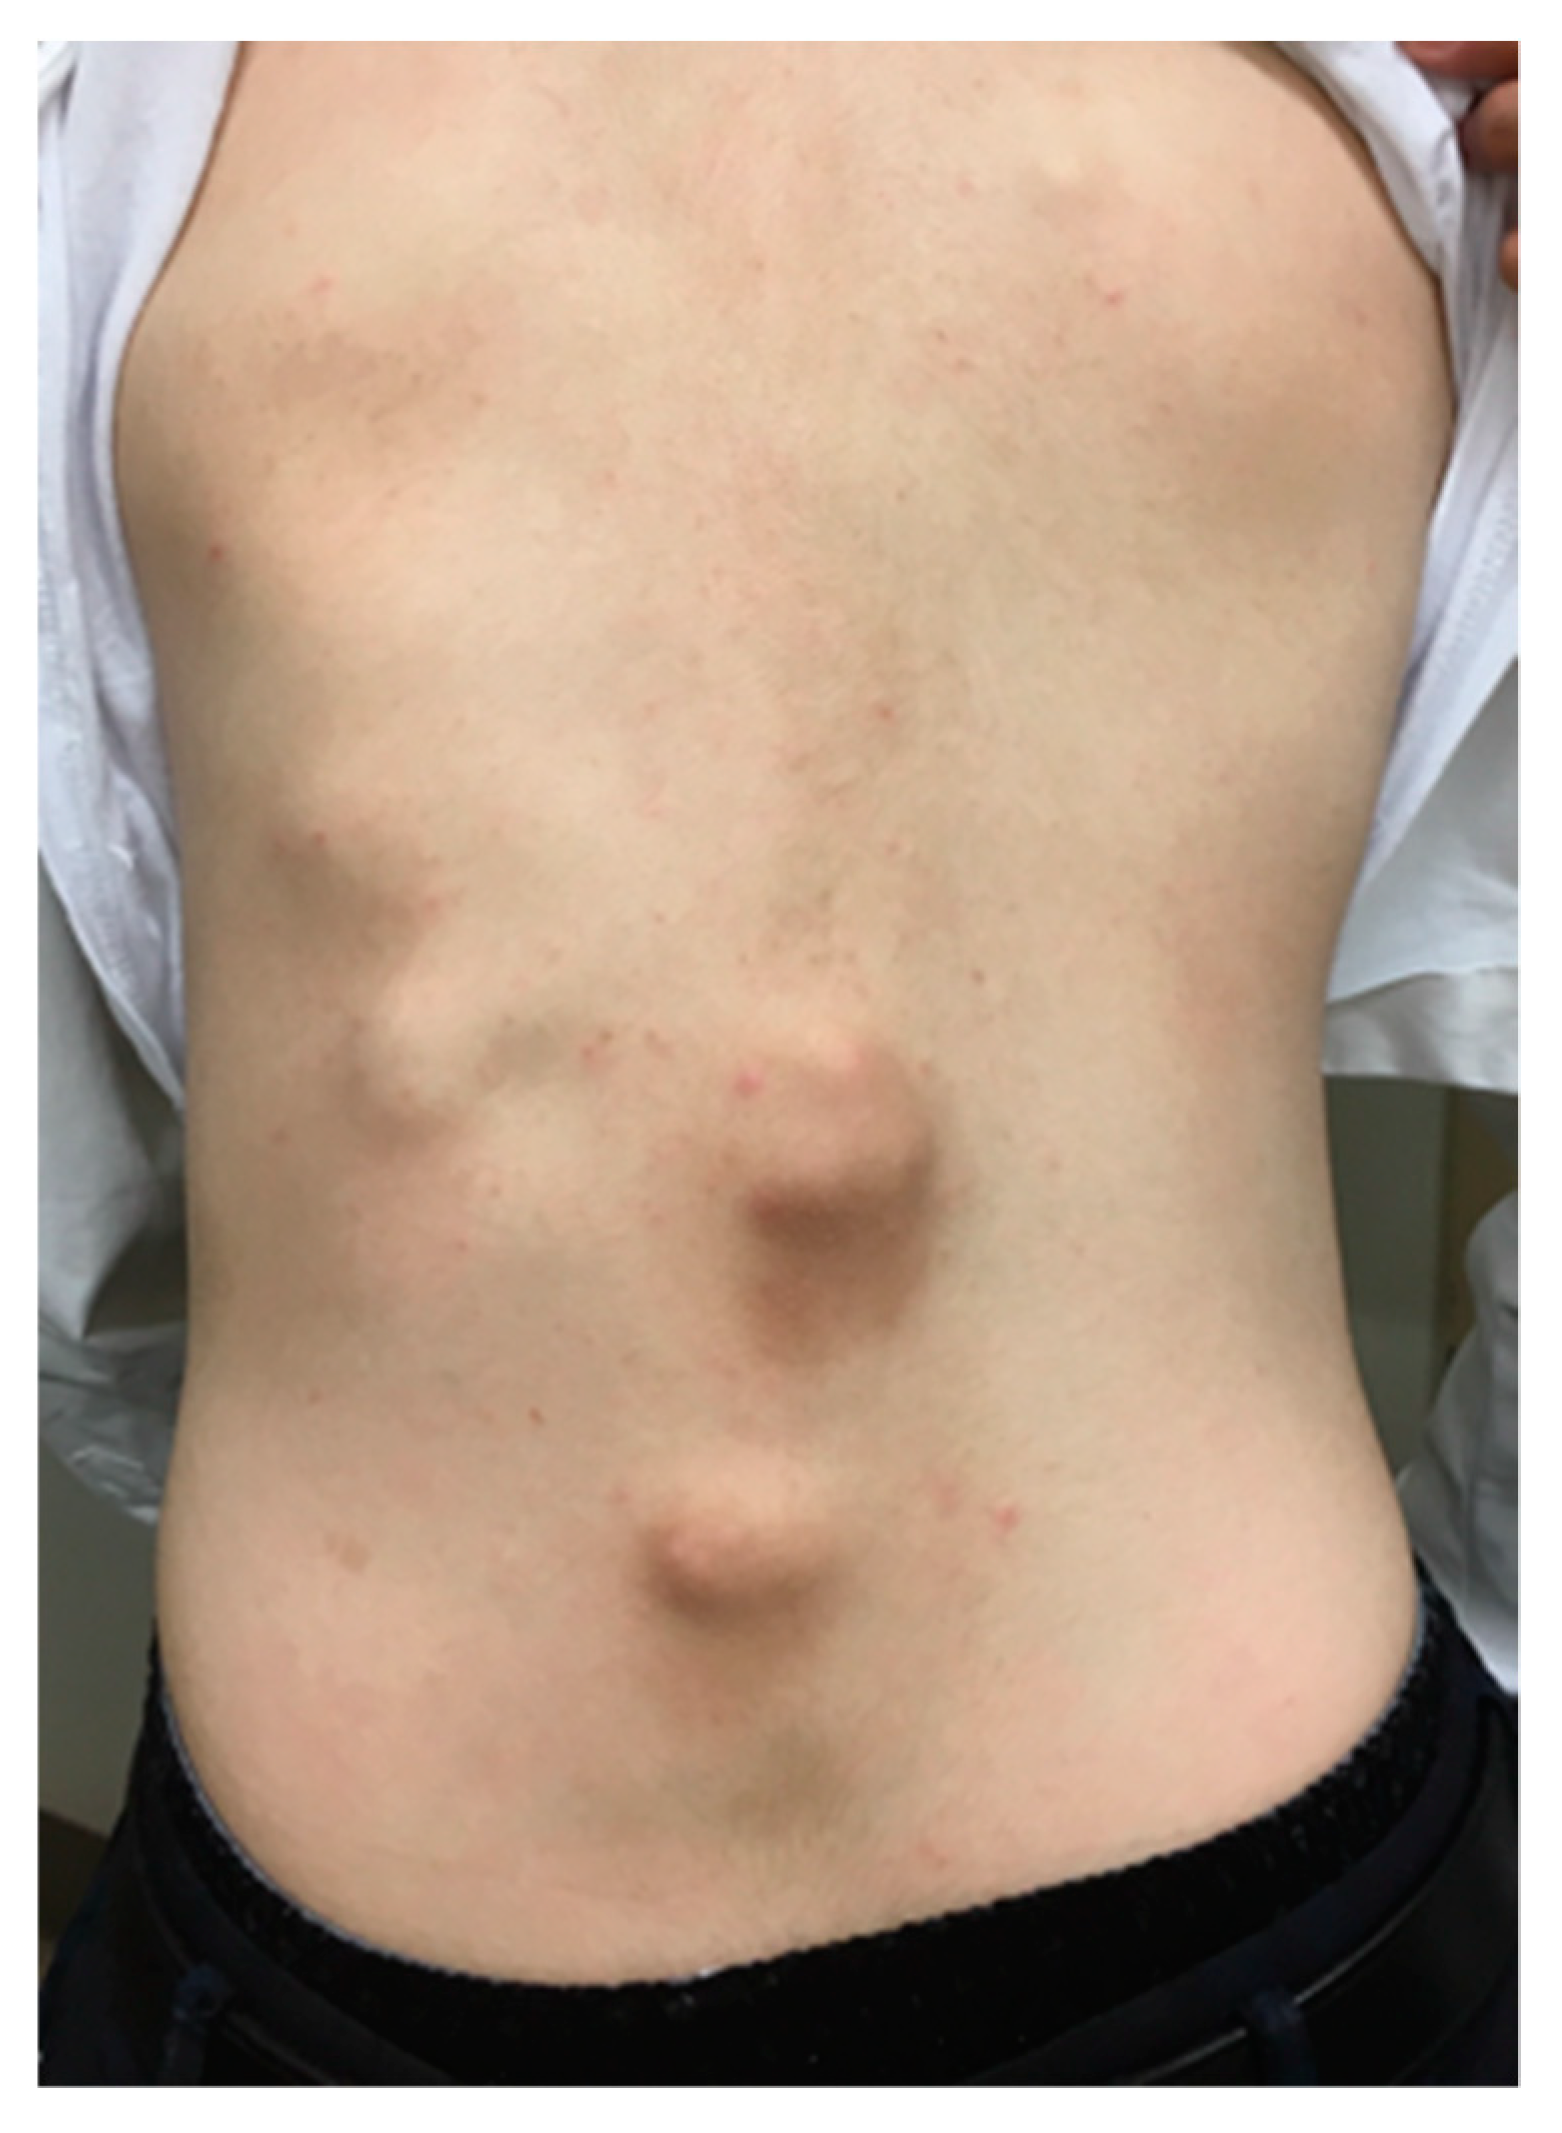

4. Natural Clinical Course

5. Skeletal Malformations